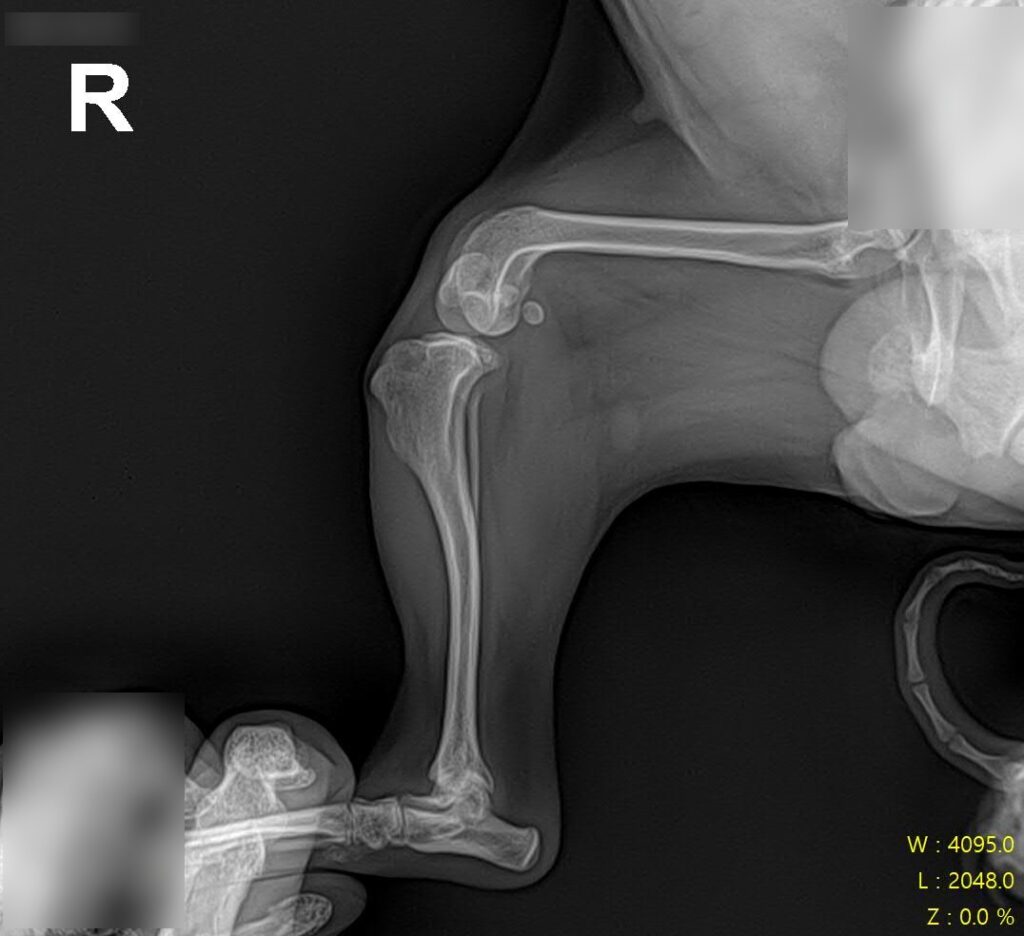

마취 전 방사선 검사 / 출처: 라온동물메디컬센터

정형학적 검사와 방사선 영상 검사를 진행한 결과, 슬개골탈구 4기(말기, terminal) 소견이 확인되었습니다. 슬개골이 완전히 고정 탈구된 상태였고, 활차구의 심각한 평탄화와 경골 조면의 내측 편위, 다리뼈의 비틀림이 동반되어 있었습니다.

2년 전 3기 진단 당시와 비교하면 그 사이 조용히, 그러나 빠르게 진행된 것이었어요. 보행이 크게 불편해 보이지 않았던 이유는 강아지가 변형된 뼈 구조에 스스로 적응하며 걷고 있었기 때문입니다.